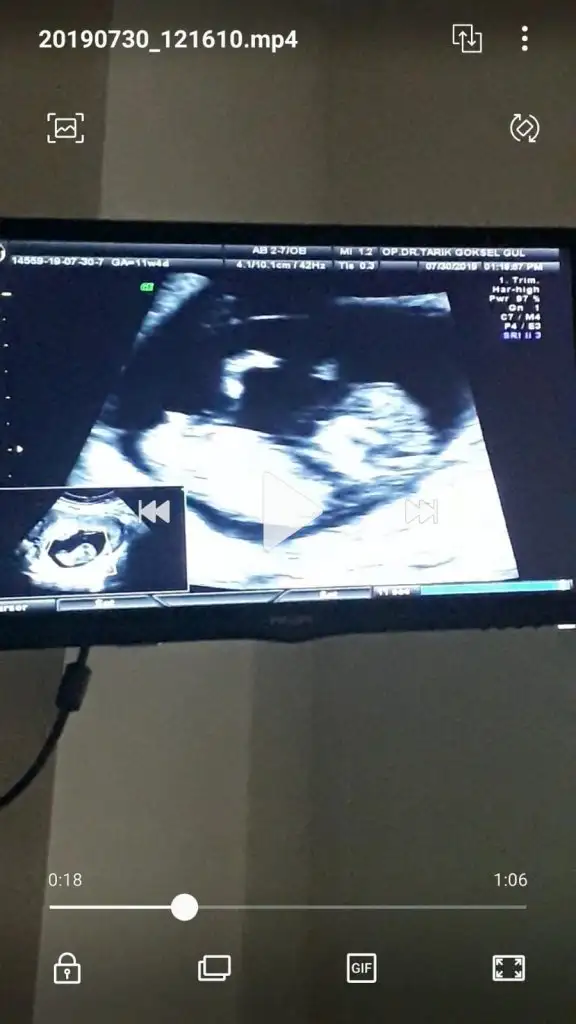

Kızlaar bende çok merak ediyorum geçen hafta 11+5 ken bunlar İpucu veriyormu sizce cinsiyet nedir?

Eki Görüntüle 2294671

Siz erkek istiyordunuz galiba.nub çizgisine ve kafa yapısına göre yorum yapıyorum.cinsiyet oluşmadan önce nub çizgisi oluşur.bu çizgi paralelse kız,dik ise erkek demektir.sizin bebeğinizin nub çizgisi bariz paralel.kafa yapısı da oval.erkeklerin kafa yapısı daha yuvarlak olur. Doktor kesin erkek dedi mi size? Buda cinsel organı diye gösterdi mi? Kaç haftalıksınız şuan?Doktor organını bile gösterdi bu çıkıntı olabilir diye yine de cevabınız için teşekkür ederim merakımdan soruyorum yanlış anlamayın neye göre Tahminde bulunuyorsunuz mesela son resim tam olarak neyi gösteriyor hiçbirşey anlamadım

Evet gönlümden geçen erkek Bi tane kızım var çok ta sevinmiştim siz şimdi kesin kız deyince moralim bozuldu biraz. Şu an sat a göre 11 hafta 6 gün usg ye göre 12 hafta 6 gün. Doktor erkeğe çok benziyor çıkıntısı burada diyerek gösterdi kesin erkek demedi yüzde 80 erkek dedi ama bazen kızlarda da bu çıkıntı oluyor dedi. Hatta bu Nub teorisinden de bahsettim belli olmaz bazen dik bazen paralel bile olabilir dediSiz erkek istiyordunuz galiba.nub çizgisine ve kafa yapısına göre yorum yapıyorum.cinsiyet oluşmadan önce nub çizgisi oluşur.bu çizgi paralelse kız,dik ise erkek demektir.sizin bebeğinizin nub çizgisi bariz paralel.kafa yapısı da oval.erkeklerin kafa yapısı daha yuvarlak olur. Doktor kesin erkek dedi mi size? Buda cinsel organı diye gösterdi mi? Kaç haftalıksınız şuan?